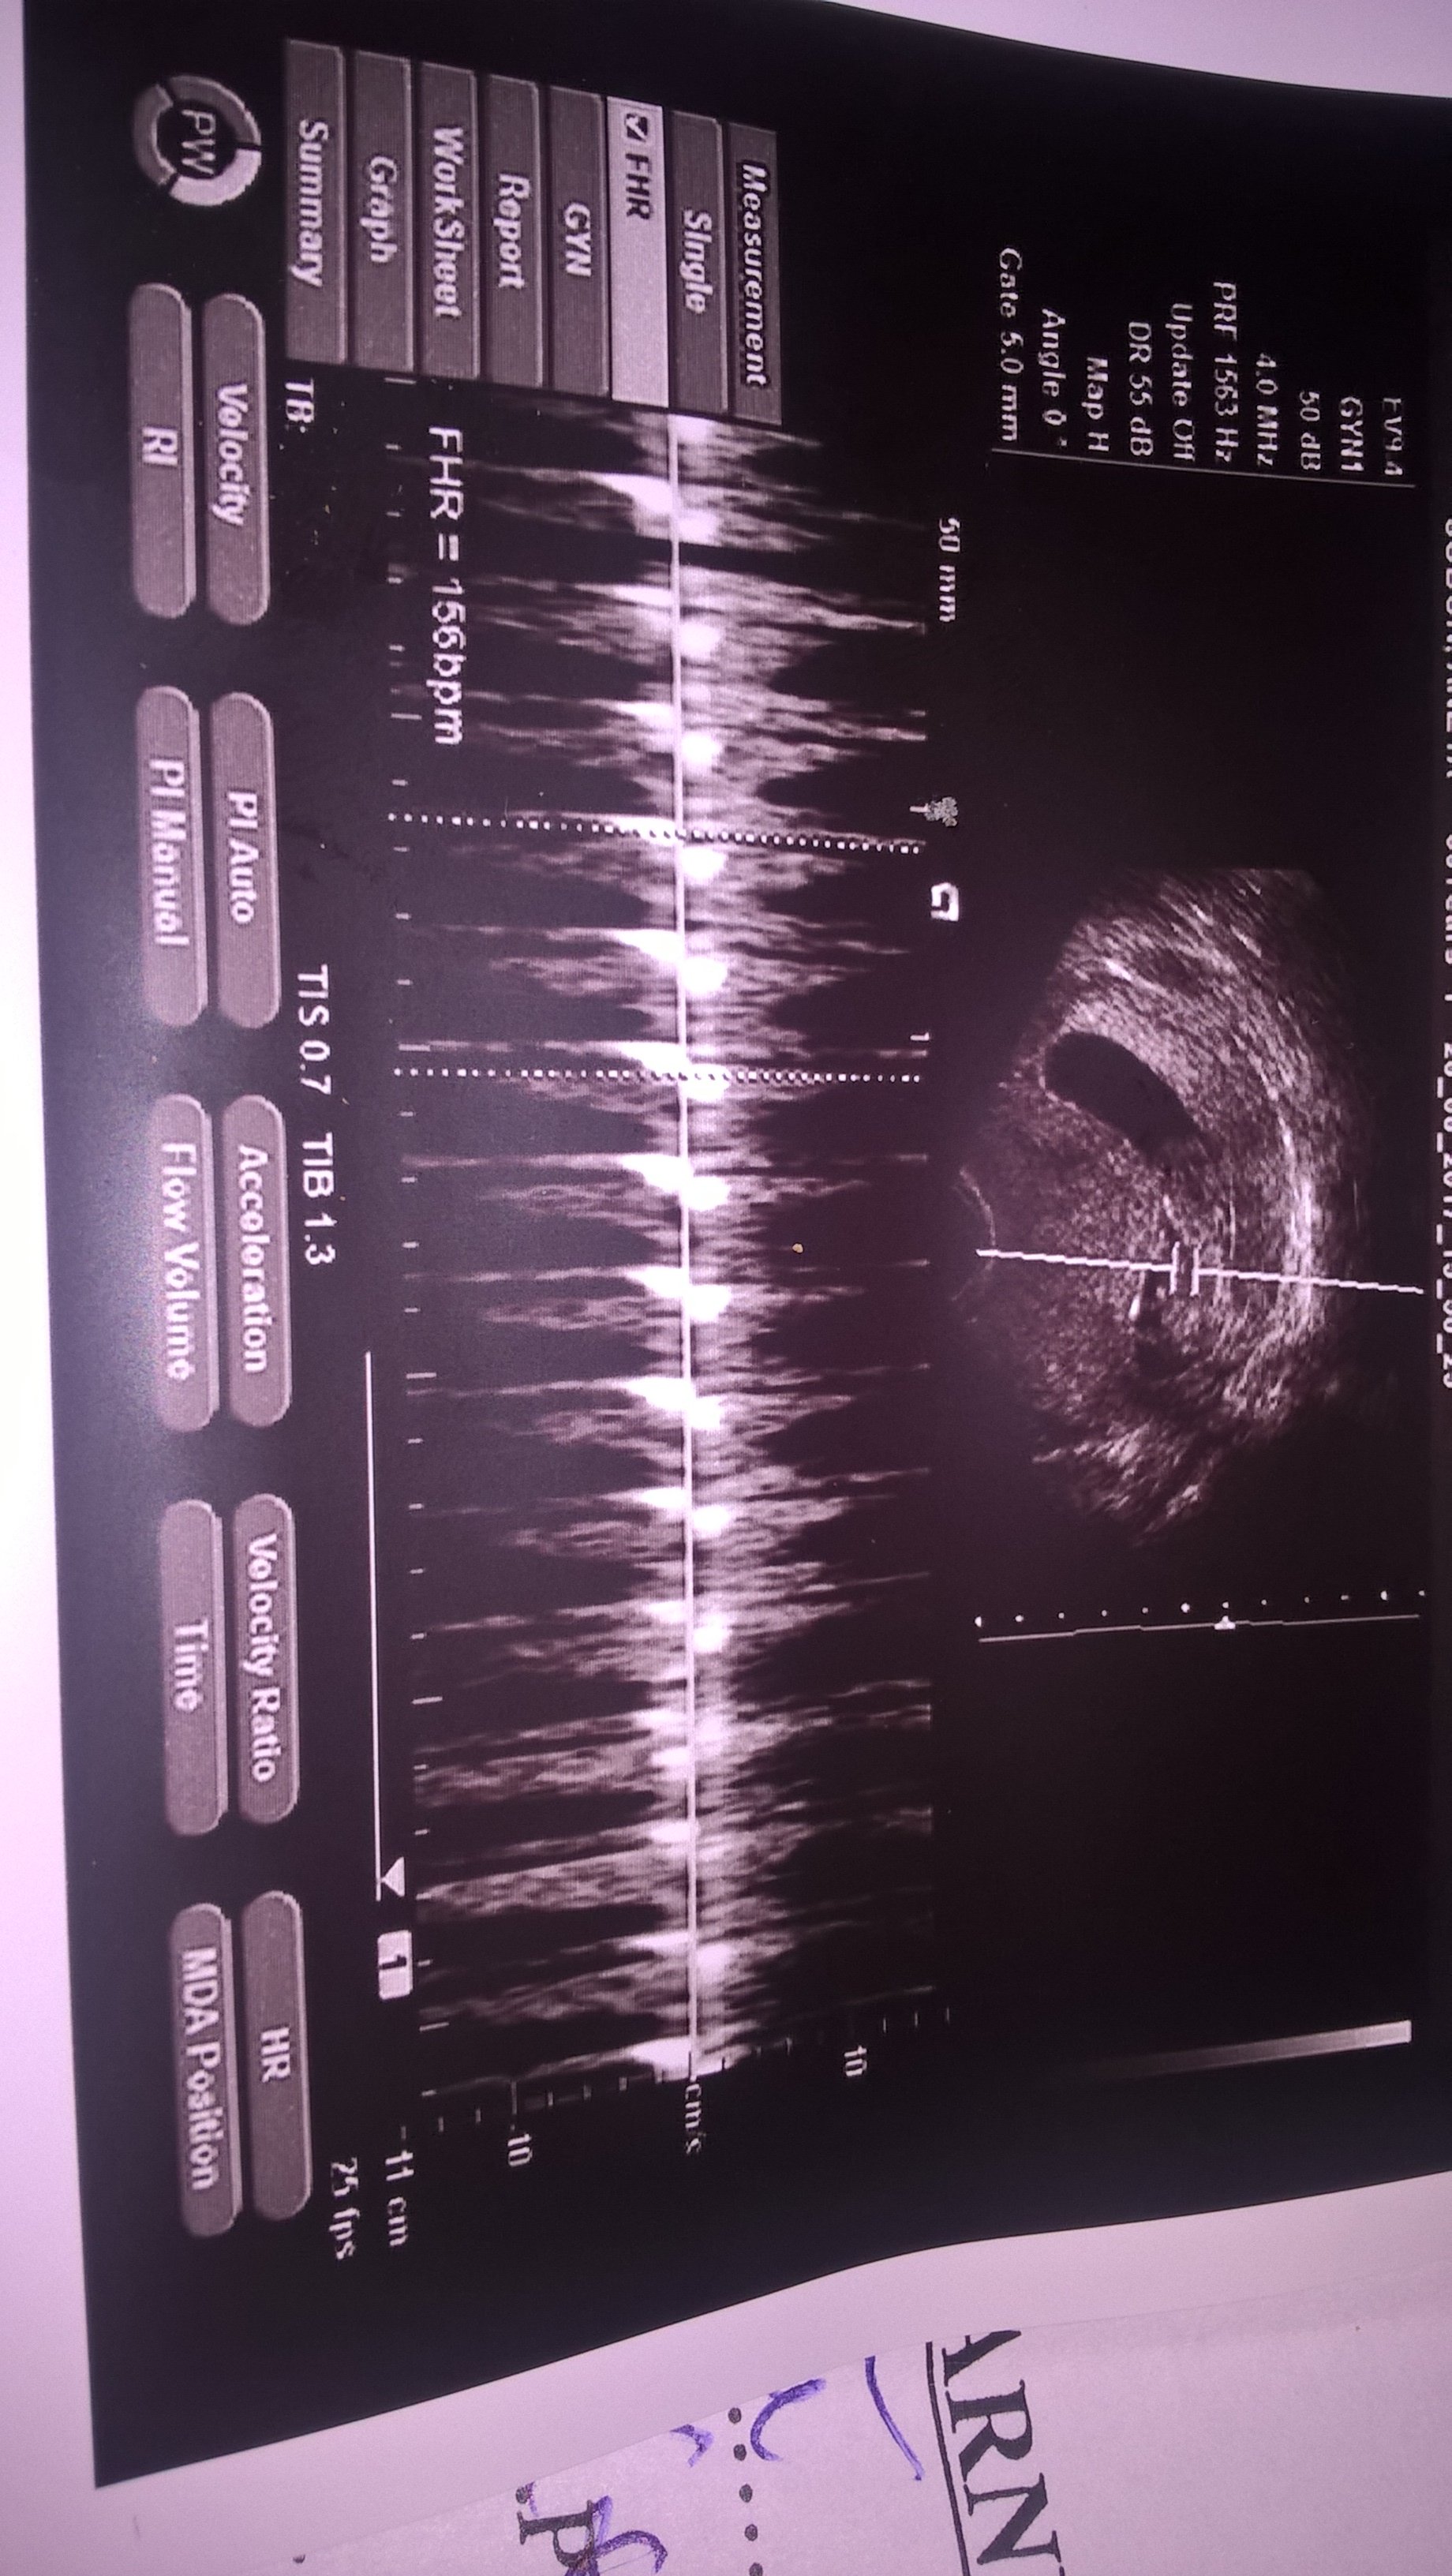

Dziekuje dziewczyny za kciukasy. Jestem po wizycie i powiem Wam ze jak zobaczyłam małego czlowieczka to sie zakochałam. Lekarz pomierzyl dlugosc .glowke i tyle:( nic nie mówił.z nim nie da sie gadac.wypisal parametry na karteczce i z tym musze sie zgłosić do swojej lekarki jutro.musze za jakis czas iść prywatnie- wiem ze z chłopcami prywatnie dokladnie mi wszystko pomierzyli .kosc nosowa otp. Tu nic- państwowo:( nawet nie wiem czy wszystko ok

to moje zdjęcia i opis

Załączniki

• WP_20170828_15_25_06_Pro.jpg

WP_20170828_15_25_06_Pro.jpg

730,4 KB · Wyświetleń: 103

z pierwszym chodziłam prywatnie i nie byłam zadowolona.z drugim na nfz ale dodatkowo usg robiłam prywatnie.i teraz tez usg bede robić prywatnie a te na nfz beda dodatkowe.czy ja dobrze widzę czy dziecko ma 12t 1dzien czyli wypadaniejsze